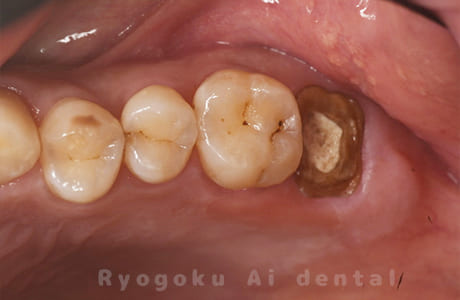

Case12

-

- 原因

- 縁下カリエス

- 治療内容

- クラウンレングスニング、ジルコニアクラウン修復

- 治療費用

- 約220,000円

被せ物の中から臭いがするとのことで、被せ物を外したところ大きな虫歯となっていました。このまま被せてしまうと被せ物が外れやすいため、埋まっている歯を出すためのクラウンレングスニング処置を行い、その後、ジルコニアクラウンで被せ物を行いました。